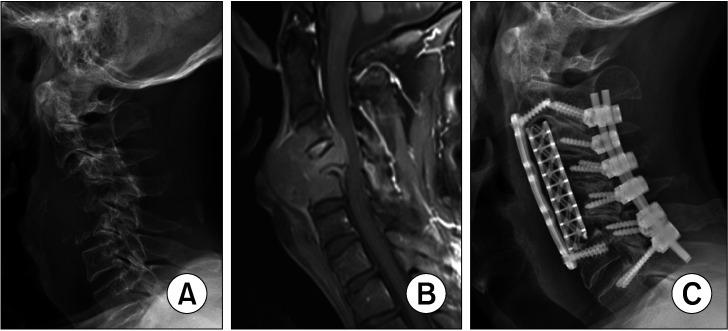

Radiation therapy (RT) performed before anterior cervical spine surgery (ACSS) may cause fascial plane fibrosis, decreased soft-tissue vascularity, and vertebral body weakness, which could increase the risk of esophageal and major vessel injuries, wound complications, and construct subsidence. Therefore, this study aimed to evaluate whether preoperative RT performed for metastatic spine cancer (MSC) at the cervical spine increases perioperative morbidity for ACSS.

Forty-nine patients who underwent ACSS for treatment of MSC at the cervical spine were retrospectively reviewed. All the patients underwent anterior cervical corpectomy via the anterior approach. Patient demographics, surgical factors, operative factors, and complications were recorded. Results of patients who were initially treated with RT before ACSS (RT group) were compared with those who did not receive RT before ACSS (non-RT group).

Eighteen patients (36.7%) were included in the RT group, while the remaining 31 (63.3%) were included in the non-RT group. Surgery-related factors, including operation time ( = 0.109), estimated blood loss ( = 0.246), amount of postoperative drainage ( = 0.604), number of levels operated ( = 0.207), and number of patients who underwent combined posterior fusion ( = 0.768), did not significantly differ between the 2 groups. Complication rates, including esophageal injury, dural tear, infection, wound dehiscence, and mechanical failure, did not significantly differ between the RT and non-RT groups. Early subsidence was significantly greater in the non-RT group compared to that in the RT group ( = 0.012).

RT performed before surgery for MSC does not increase the risk of wound complication, mechanical failure, or vital structure injury during ACSS. The surgical procedural approach was not complicated by previous RT history. Therefore, surgeons can safely choose the anterior approach when the number of levels or location of MSC favors anterior surgery, and performing a posterior surgery is unnecessary due to a concern that previous RT may increase complication rates of ACSS.